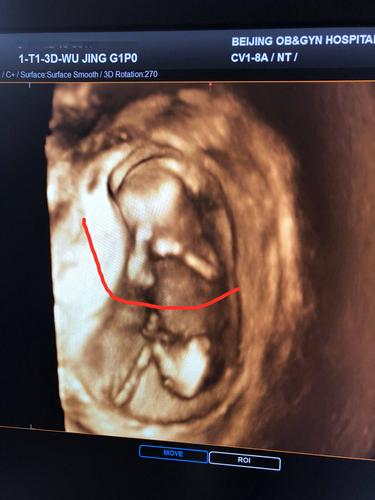

孕13周,nt顺利通过,可以看到宝宝的小人型啦,在揉眼睛好像!

孕13周NT男孩图

13周男孩b超图片

孕13周男女b超区别图